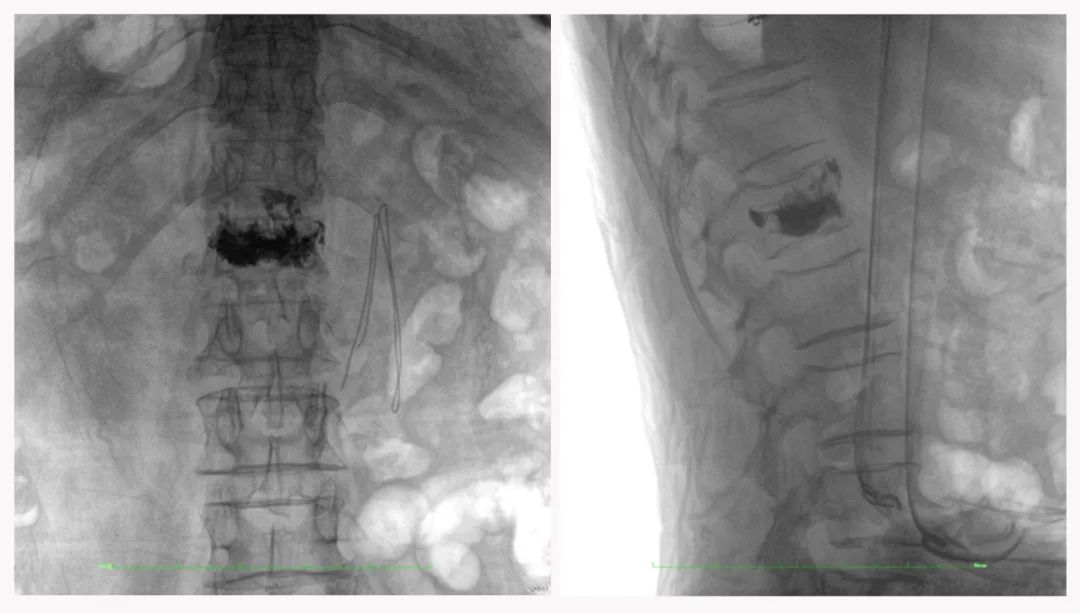

二維正側位影像

三維“類CT”影像

在臨床使用中,三維C形臂能看到二維影像所觀察不到的信息:

二維C形臂提供的影像存在固有局限性,其成像原理是基于單一方位的投影,導致深部解剖結構信息缺失,且容易受到骨骼和組織的重疊干擾,使得部分病灶難以清晰顯示,甚至被掩蓋。相比之下,三維C形臂通過三維重建技術,可以獲得類似CT的斷層掃描圖像,從而解決了二維影像的重疊問題。

醫生能夠利用這些三維圖像,更直觀、更深入地分析病變,進行全方位觀察,例如:精確評估骨折復位情況、清晰顯示內植入物的位置及其與周圍組織的關系等。尤其在復雜骨折、脊柱手術、呼吸介入等臨床場景中,三維C形臂提供的詳細信息對手術導航和療效評估至關重要。